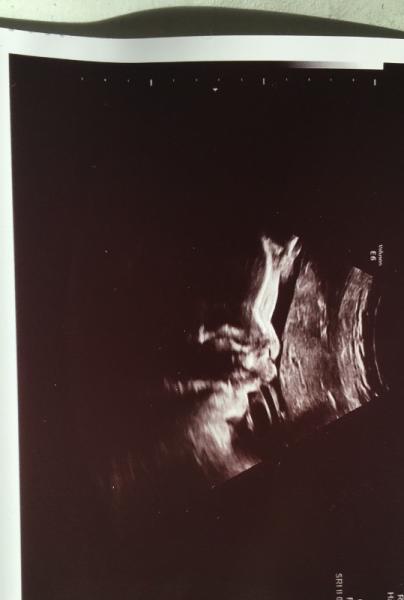

Huhu ihr Lieben, komme gerade wieder vom FA-Termin und Babyboy wiegt schon 2,1 kg bei 42cm in SSW 31+2. Kopf ist auch schon tief unten und der Gebärmutterhals bei 3,5 cm Ich werd jetzt langsam schon total hipplig den kleinen Mann kennenzulernen. Bin so gespannt wie er aussieht

Bild zu Frauenarzttermin - Forum für April - Mamis